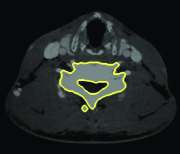

Appearance is one of the most important visual cues to distinguish between different structures in an image. Appearance is described by studying the distribution of different features such as intensity values in gray-scale images, color, and texture inside each object. In most cases, appearance models are incorporated into the data term in (2) and (7). The purpose of incorporating appearance prior is to fit the appearance distribution of the segmented objects to the distribution of objects of interest, e.g. using Gaussian mixture model (GMM) (Rother et al., 2004). In the literature, there are two ways to model the appearance: 1) adaptively learning the appearance during the segmentation procedure, and 2) knowing the appearance model prior to performing segmentation (e.g. by observing the appearance distribution of the training data). In the former case, the appearance model is learned as the segmentation is performed (Vese and Chan, 2002) (computed online). In the second case, it is assumed that the probability of each pixel belonging to particular label is known, i.e. if represents a particular set of feature values (e.g. intensity/color) associated with each image location for object, then it is assumed that is known (or pre-computed offline). This probability is usually learned and estimated from the distribution of features inside small samples of each object. Figure 9 illustrates the probability of different structures (the kidney, the tumour, and the background) in an endoscopic scene. A lower intensity in Figures 9(b-d) corresponds to higher probability.